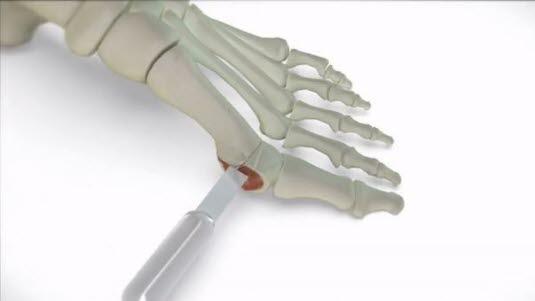

Den vanligste metoden er at stortåens mellomfotsben deles og forskyves (osteotomi) slik at skjevheten rettes opp. Kirurgen lager et brudd i beinet, fjerner en kile av beinet slik at retningen på tåen endres. Dette bruddet må gro. Du må gå med gips på foten i 6-8 uker eller en ortose eller spesialsko. Kontroll avtales på poliklinikken på dette tidspunkt. På kontrollen fjernes gipsen, og stingene etter operasjonen blir tatt.

Copyright beskyttet bilde. Kun brukt til å vise til hallux valgus operasjon på YouTube.Se animasjon som beskriver en hyppig anvendt operasjonsmetode (engelsk tale).